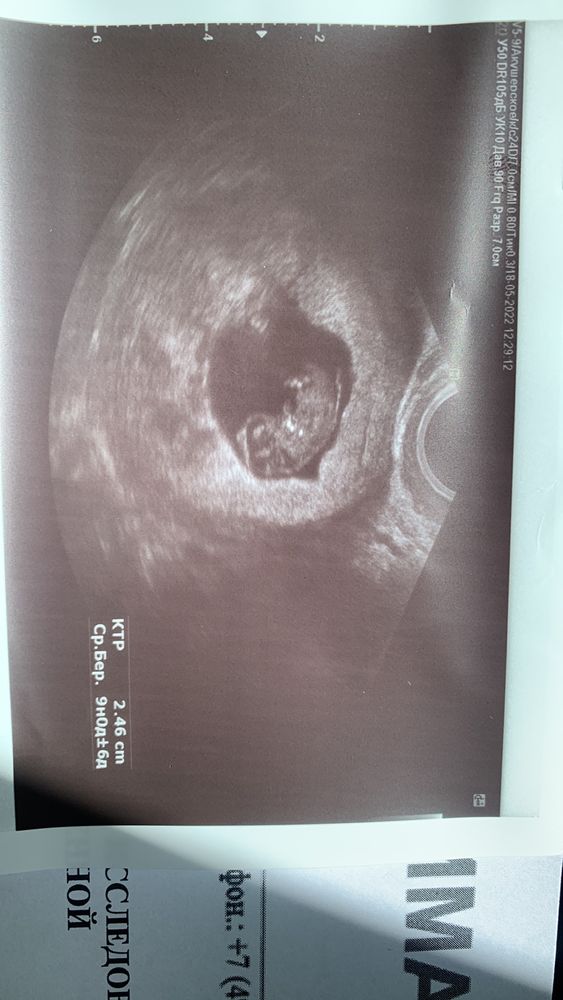

Я ровно в 9 недель была на узи, где все хорошо, сердцебиение и малыш 25 мм, срок 9 недель и по узи тоже…,

Вот такой малыш)